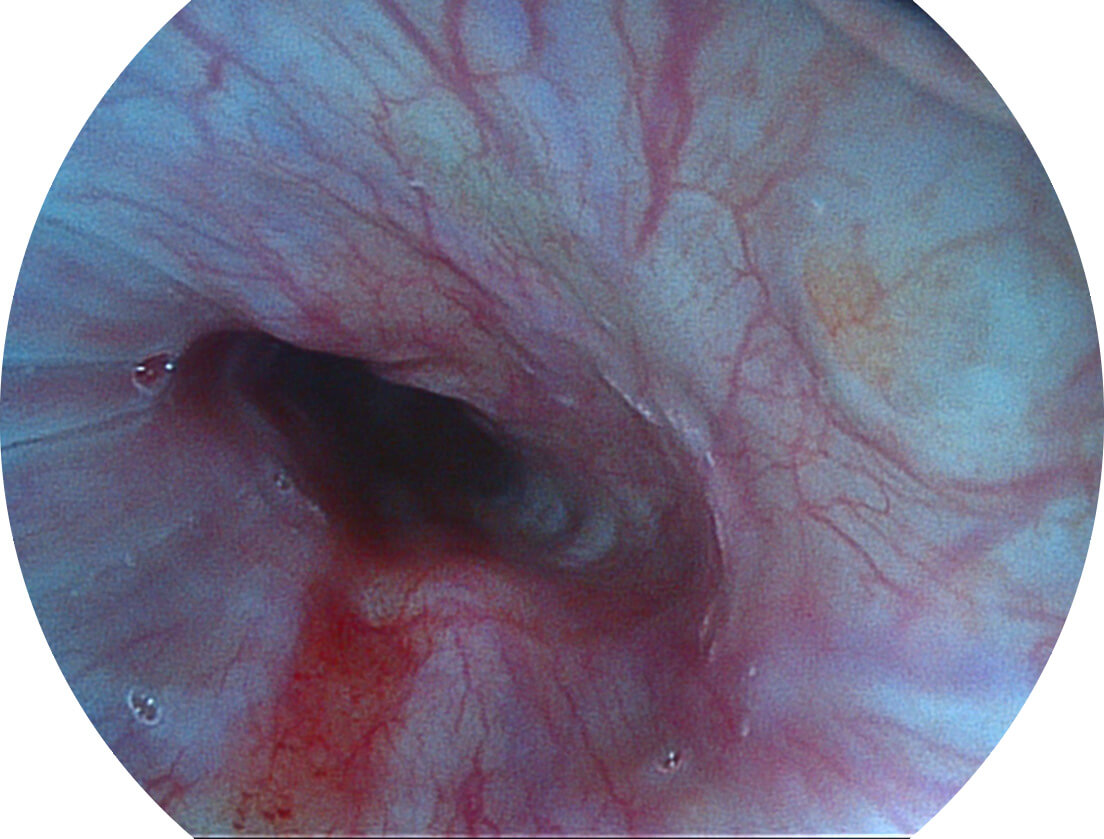

白光图像

SFI图像

图像具有高亮度、高黏膜血管颜色对比度的特点,且不改变粘液、食物残渣、粪便的基本颜色,可在中远景下进行观察,助力消化道早期疾病的诊断。

采用光路合束技术,光谱自由度高,实现了更丰富的照明模式,染色模式SFI及VIST,从远景到近景,助力消化道早期疾病诊断。